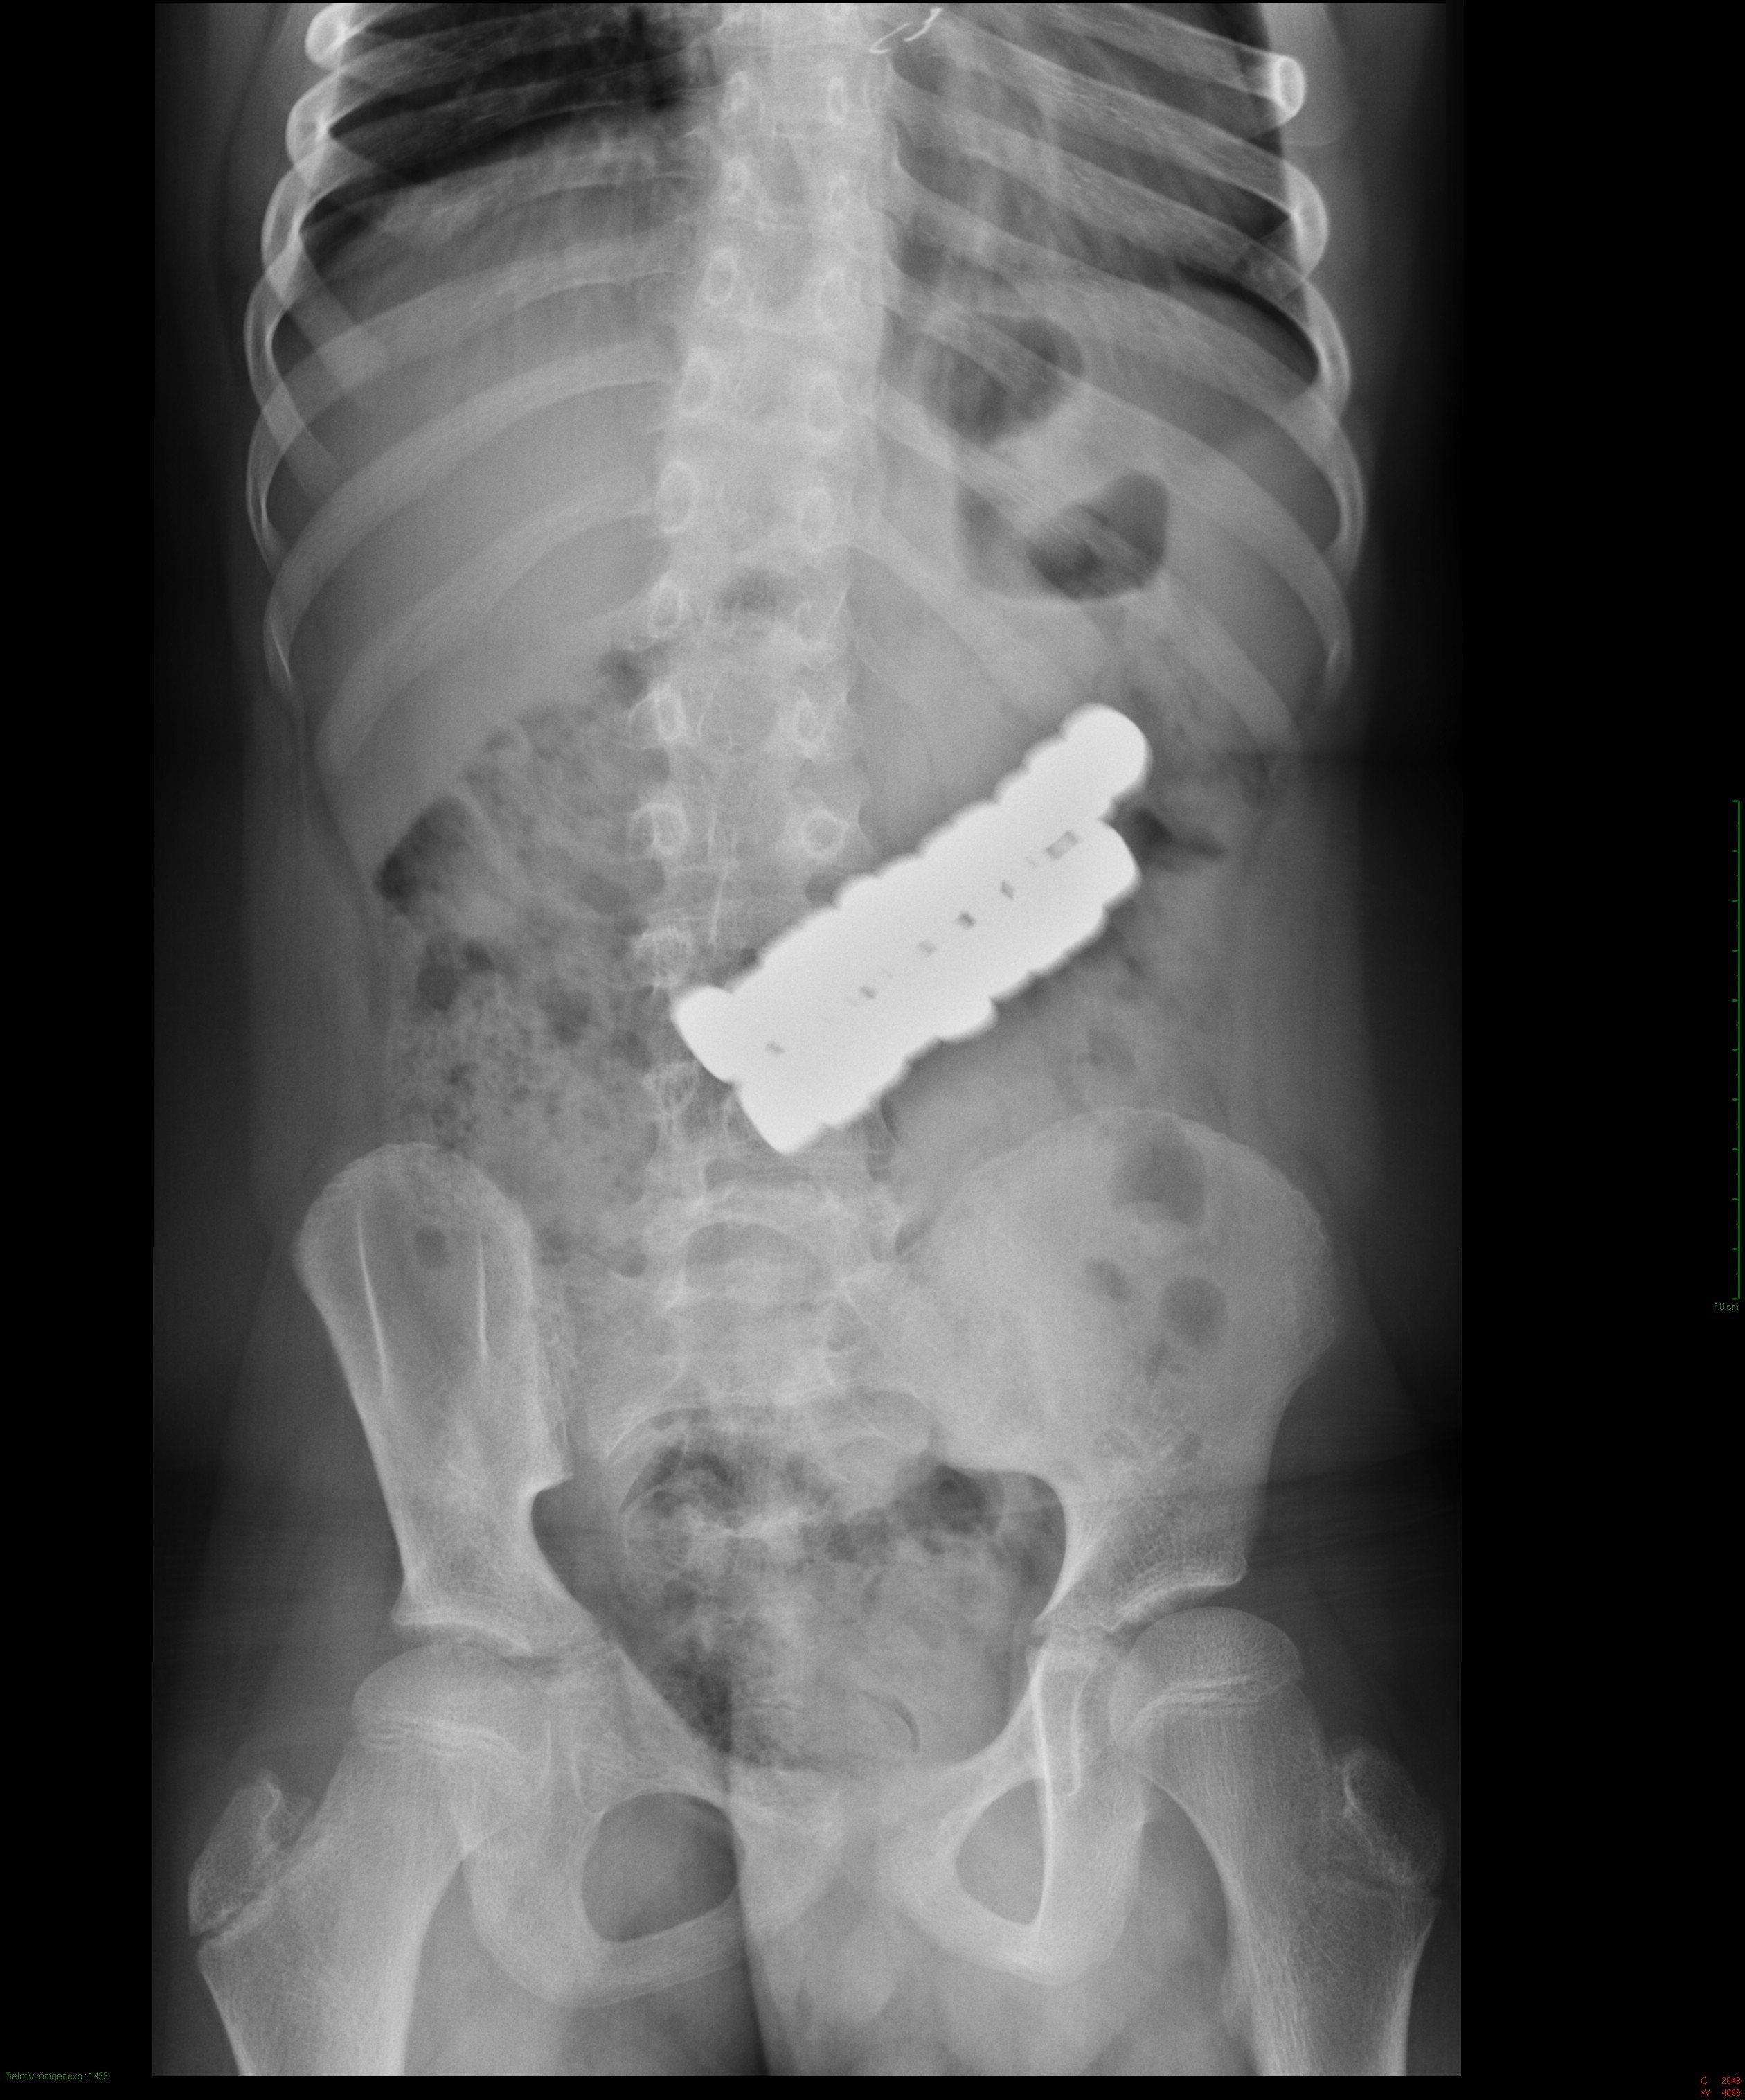

Intézetünkbe egy 10 éves gyermek került, aki 20 darab kavics nagyságú mágnest nyelt le. Szerencsére nem volt panasza, fájdalmat sem jelzett. A röntgenvizsgálat során azt láttuk, hogy a mágnesek egy csomóban, egymáshoz kapcsolódva a gyomorban helyezkednek el.

Az endoszkópos kollégák száloptikás eszközzel lejutottak a gyomorba, azonban az erősen összetapadt mágnesek egyenként nem voltak eltávolíthatóak, így a műtét mellett döntöttek.